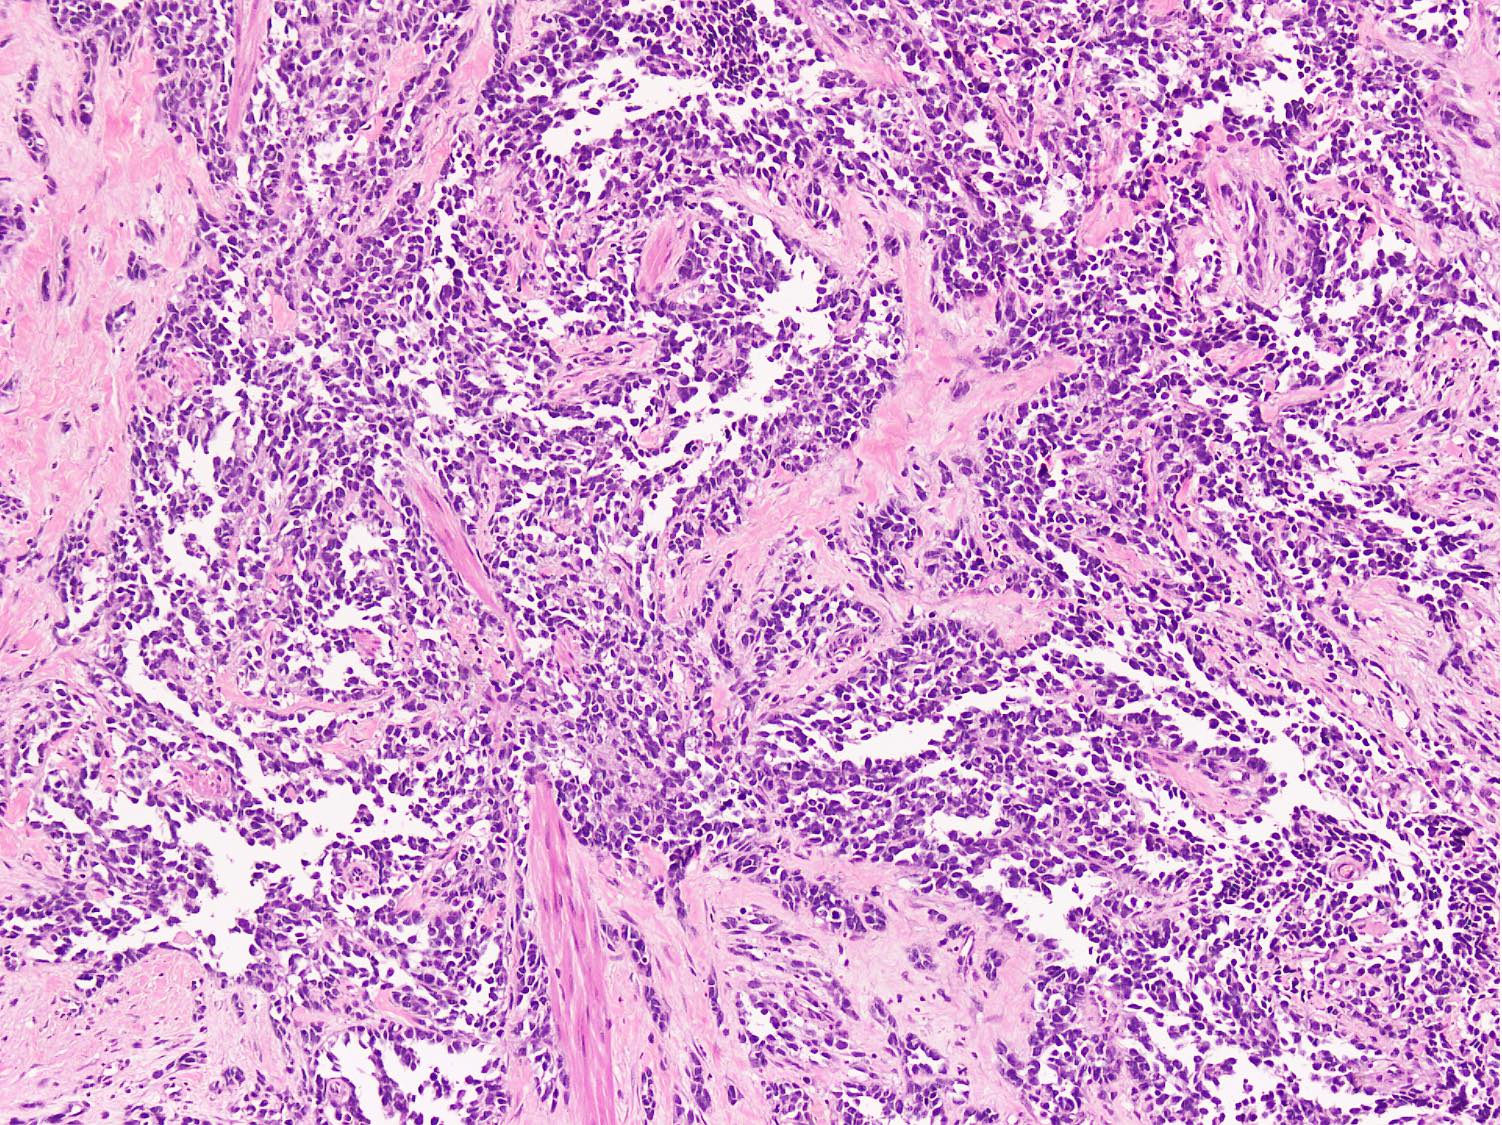

Microscopic (histologic) description

- Cellular round cell tumor

- Large clusters, nests, cords and trabeculae of primitive round cells, separated by variably thick fibrovascular septa

- Loss of cellular cohesion in the center forms alveolar-like, cystic and vague papillary appearance (Histopathology 2022;80:98)

- Layer of cells adheres to the periphery of the spaces and fibrous septa

- Small to intermediate sized monomorphic cells with scant cytoplasm

- Hyperchromatic nuclei with variable conspicuous small nucleoli

- Cells in the center have poor preservation and are necrotic; may appear floating

- Multinucleated tumor giant cells with wreath-like lineup of nuclei are common (Acta Pathol Microbiol Immunol Scand A 1982;90:345)

- Round to oval rhabdomyoblasts with abundant acidophilic cytoplasm may be present

- Brisk mitosis and variable tumor necrosis

Microscopic (histologic) images

Contributed by Nasir Ud Din, M.B.B.S.

- Comment: Histology shows an infiltrative cellular tumor composed of large clusters and nests of primitive round cells, separated by variably thick fibrovascular septa. Irregular pseudoalveolar spaces and cystic change are present within the nests. Scattered wreath-like multinucleated giant cells and rhabdomyoblasts are present along with brisk mitosis and necrosis. Tumor cells show strong and diffuse desmin and myogenin expression, focal MyoD1 and alpha smooth muscle actin positivity, whereas CD34, S100, CK AE1 / AE3, CD99, SALL4, LCA, TdT and synaptophysin are negative. Morphological features and immunoprofile strongly support the diagnosis of alveolar rhabdomyosarcoma. It is a malignant high grade soft tissue sarcoma with myogenic differentiation and an overall worse prognosis.